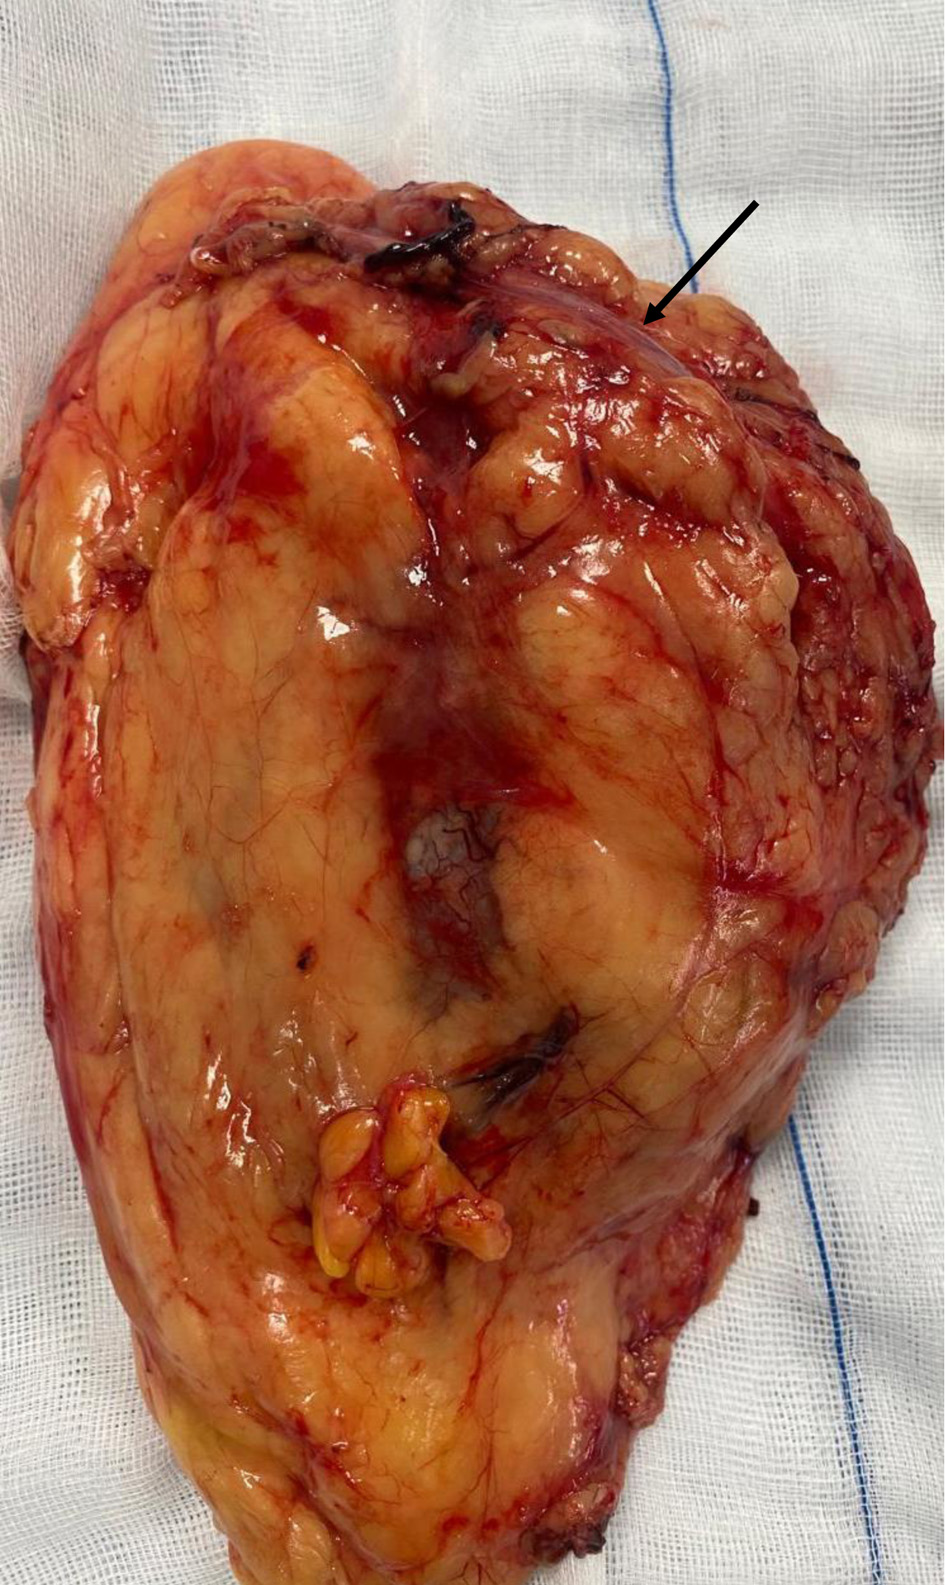

Preoperative evaluation included transthoracic echocardiography, which confirmed severe AS (with a transvalvular mean gradient of 76 mm Hg, and maximal velocity of 5.75 m/s) with preserved left ventricular systolic function (Fig. 1). Laboratory results showed mild anemia and biochemistries consistent with stable chronic kidney impairment. Cardiologic and anesthetic consultations concluded that although perioperative risk was high, surgical treatment represented a reasonable option given the patient’s goals and expected disease progression. A multidisciplinary conference involving anesthesiology, urology, gynecology, nephrology, and intensive care specialists was convened, and an individualized perioperative plan was developed emphasizing tight hemodynamic control, restrictive yet goal-directed fluid administration, and early postoperative recovery strategies.

Figure 1. Severe aortic stenosis with a transvalvular mean gradient of 76 mm Hg and maximal velocity of 5.75 m/s (arrows indicates transvalvular mean gradient and maximal velocity).